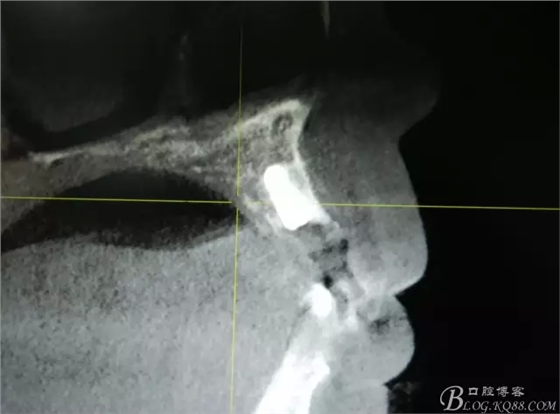

患者、楊xx、男、49歲。主訴:左側(cè)前牙拔除半年,活動(dòng)義齒修復(fù)四個(gè)月,要求種植修復(fù)。??茩z查:21缺失,牙槽粘膜厚度正常。CBCT檢查:高度16mm,寬度7mm.術(shù)前簽知情同意書。

圖1.術(shù)前的CBCT檢查:22缺失。

圖2.CBCT的三維成像及縱剖面、水平面影像

圖11.術(shù)后的CBCT檢查: